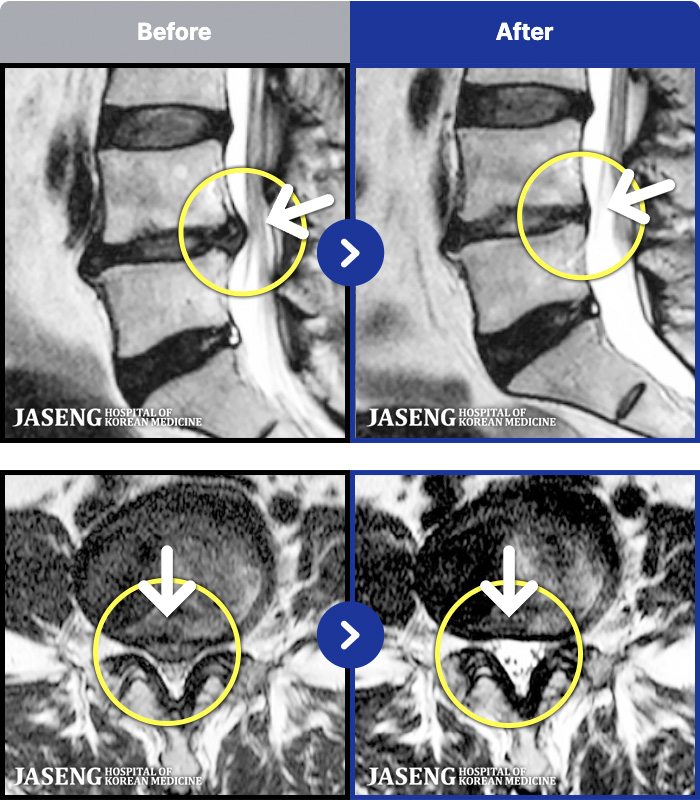

1,298 MRI ũ ʸ Ȯϼ.

[] 23.11.11~25.06.04